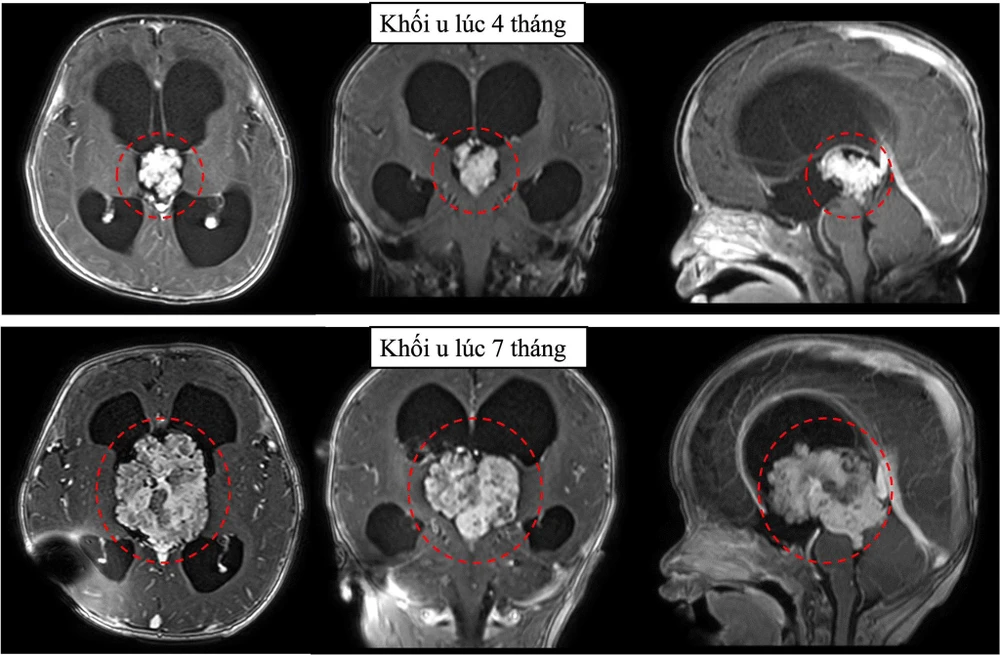

Ảnh chụp phim cho thấy u não phát triển rất nhanh, tăng kích thước hơn gấp 3 lần sau 3 tháng. Ảnh: BVCC

Hình ảnh cộng hưởng từ sọ não ghi nhận khối u vùng não thất 3 gây chèn ép dẫn đến não úng thuỷ tắc nghẽn. Khối u nằm vị trí não thất 3, vị trí sâu với nhiều cấu trúc thần kinh quan trọng xung quanh, là một trong những vị trí can thiệp rất khó trong phẫu thuật sọ não.

Tuy nhiên, phim cộng hưởng từ sọ não 3 tháng sau cho thấy u não phát triển rất nhanh, tăng kích thước gấp 3 lần. Không thể trì hoãn thêm, bác sĩ khoa Ngoại thần kinh đã tư vấn gia đình phẫu thuật mổ lấy u để kịp thời cứu bệnh nhi.